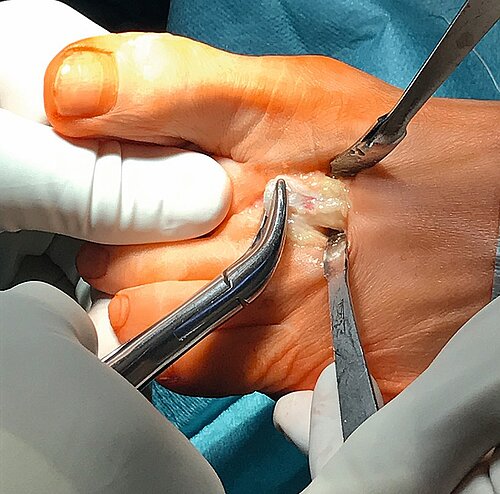

Definition: Die Versteifung des Großzehengrundgelenkes erfolgt in Funktionsstellung (Abb. 12), also in 10 Grad Dorsalflexion und 10 Grad Valgusstellung [25].

Indikation: bei jüngeren Patienten mit ausgeprägter Arthrose des Großzehengrundgelenkes Grad 3 und 4 und deutlicher Bewegungseinschränkung.

OP-Technik: Mediodorsaler Hautschnitt, Eröffnung der Kapsel von Mitte des Basisgliedes bis 2–3 cm proximal des Großzehengrundgelenkes, Darstellung des Gelenkes und Einbringen eines zentralen Führungsdrahtes achsgerecht ins Metatarsale 1. Einbringen der Cuff and Cone-Fräse und Entknorpeln des Großzehengrundgelenkkopfes (Abb. 13) sowie entsprechendes Vorgehen am Basisglied.